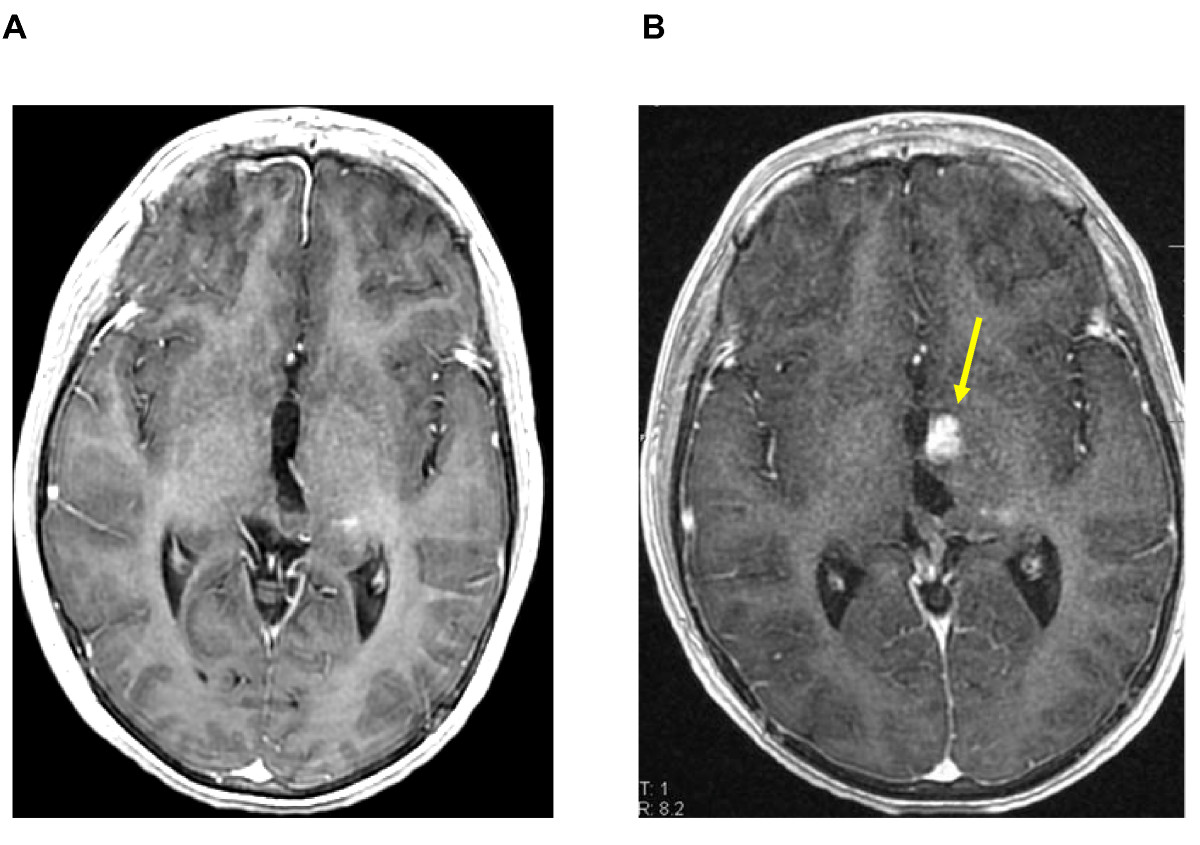

Figure 4. Nine months after irradiation: complete disappearance of the contrast enhancement (left) and no detectable Permeability (right).

[A] T1-weighted transaxial MR image after administration of iv Gd-DTPA and [B] the superimposed Permeability map, with no contrast enhancement or detectable microvascular leakage. To be noted, a subtle hypersignal, pre-existing to the irradiation, as a post-operative modification (yellow arrow).